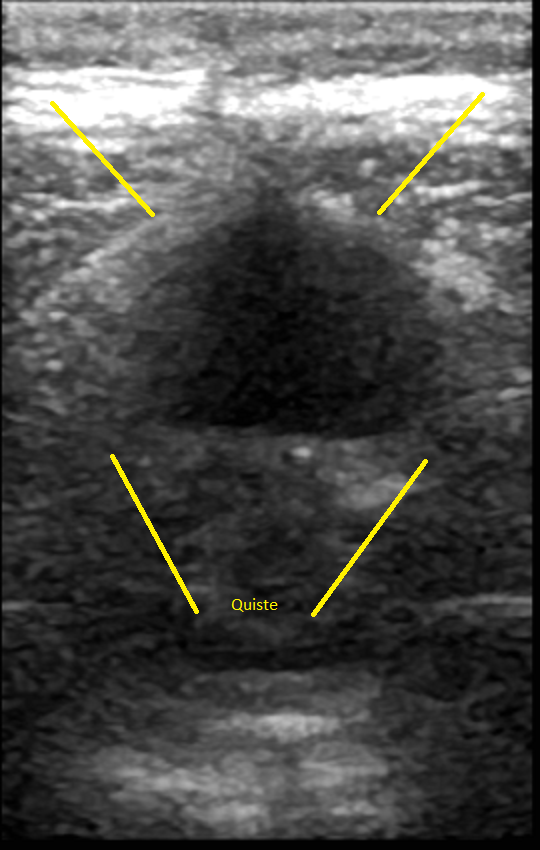

En noviembre 2019 6.8 x 3.5 x 1.6 cm y 20 centímetros cúbicos.

En enero del 2020 5.5 x 2.4 x 1 cm y 7.6 centímetros cúbicos

27 Julio 2020 4.1 x 3.0 x 1.6 cm y 11.04 centímetros cúbicos y un trayecto fistuloso de 0.7 cm.

Siguiendo la curva de disminución el quiste debió ser mínimo, pero aumento 4 centímetros cúbicos, no quiso ni abrir el sobre con los resultados, porque ya los había visto, se limito a decirme "Eso no puede ser posible, si fuera cierto no te sentirías ni te verías bien", "Seguramente quién lo realizó no lo comparó con los estudios previos o no supieron cómo hacerlo" "Doctor me lo hice aquí, no creo que se hayan equivocado" "¡Pues no!, yo no puedo tomar como válido este estudio así que necesito que te hagas una resonancia de cráneo"

El 6 de agosto regresé con los resultados de la resonancia, análisis de sangre y orina, esta vez yo tuve los resultados primero, así que al verlo lo primero que dije fue "¿Qué pasa doctor que mi cuerpo sigue rechazando el parche?", la resonancia confirmó lo mismo el quiste media 4.2 x 1.7 x 2.9 cm y 10 centímetros cúbicos y la fistula 4.8 mm y el remanente del tumor es de 15.1 mm, en contraste con en el ultrasonido 4.1 x 3.0 x 1.6 cm y 11.04 centímetros cúbicos y la fistula 0.7 cm.